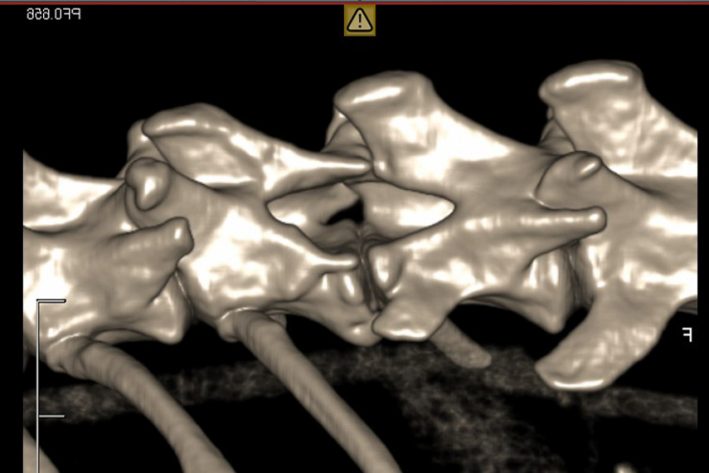

Atlantoaxiale-Instabilität: Verschiebung der ersten beiden Halswirbeln